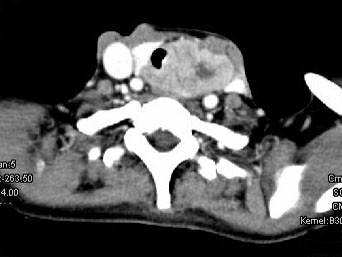

问题 女,50岁,左下颈部扪及一质硬、表面高低不平的包块,肿块逐渐增大,现感吞咽困难,CT如图所示,最可能诊断为()

选项 A.甲状腺癌 B.食管癌 C.喉癌 D.甲状腺原发淋巴瘤 E.颈部神经鞘瘤

答案 A